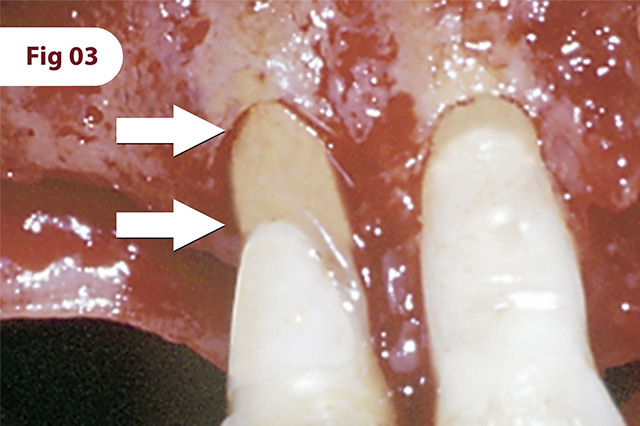

Lesão perirradicular com acentuada perda óssea vertical. Região já preparada para o processo regenerativo.

Instalação da membrana fixada sem tachinhas ou parafusos.